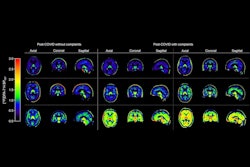

Compared with C-11 K-2 PET imaging in 80 healthy controls, a voxel-wise analysis indicated a statistically significant increase in radiotracer uptake across the brain overall as well as in specific regions of patients with long COVID, indicating increased AMPAR density, the researchers reported.

(A) Elevations in C-11 K-2 SUVR-WM in patients with long COVID memory impairment (Cog-LC) (n = 30) compared to healthy controls (HCs) (n = 80) (p < 0.05, T > 1.66, one-tailed, false discovery rate correction). (B) Multiple comparisons across Hammers’ VOIs between HCs (n = 80) and Cog-LC (n = 30). Bold line and dashed line of each plot represents mean and quartiles, respectively. *p < 0.05, **p < 0.01, ***p < 0.001 (Bonferroni multiple comparison test after two-way ANOVA analysis). (C) Brain regions showing a negative correlation between 11-C K-2 SUVR-WM and picture-naming scores of the RBANS in Cog-LC (n = 30) (p < 0.05, T > 1.71, one-tailed, false discovery rate correction). (D) Overlapping brain regions between the clusters in A and C. (E) Brain regions showing a negative correlation between 11-C K-2 SUVR-WM and figure recall scores of the RBANS in Cog-LC (n = 30) (p < 0.05, T > 1.71, one-tailed, false discovery rate correction). (F) Overlapping brain regions between the clusters in A and E. Abbreviations: A, anterior; P, posterior; R, right; L, left; FDRc, false discovery rate correction. Courtesy of Brain Communications

In addition, brain regions where C-11 K-2 tracer was significantly increased were negatively correlated with long-COVID patients’ picture naming and figure recall scores, which are RBANS subcategories, according to the results.